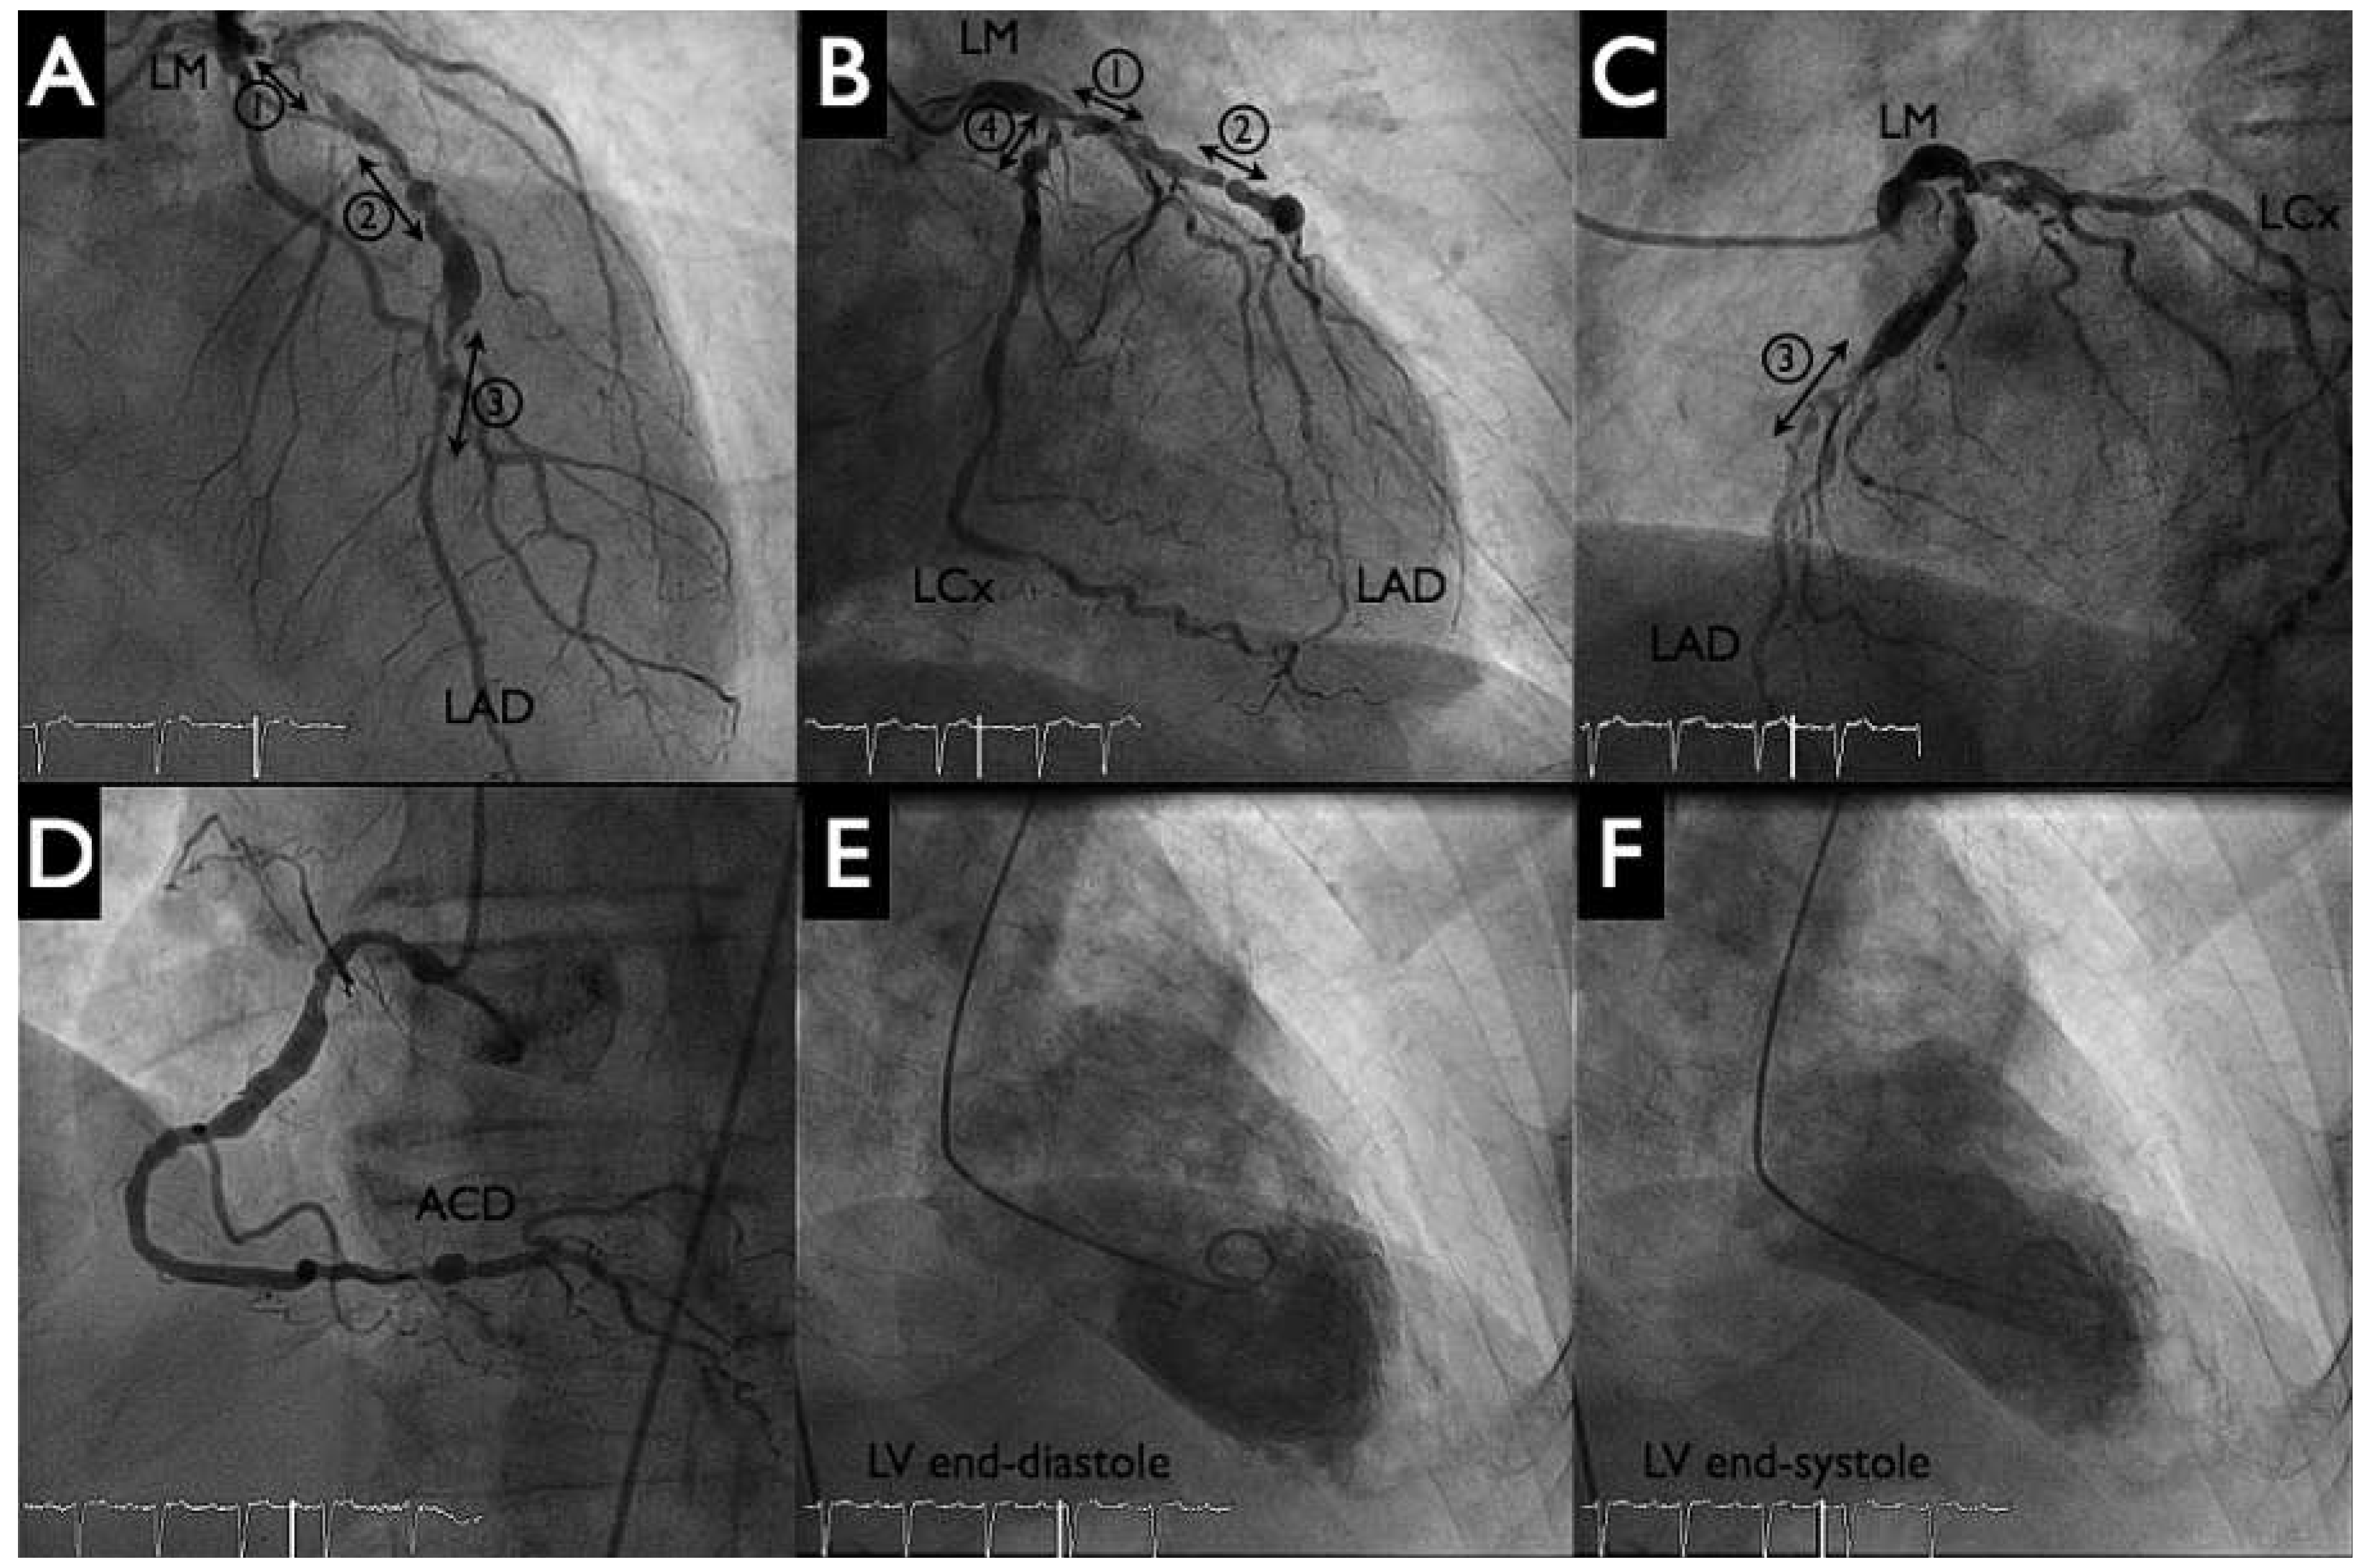

Following this, the pigtail catheter was exchanged for a 6 Fr Q4 guiding catheter with PCI of the distal left anterior descending artery (LAD) (SYNERGY II 2.25–20 mm, Boston Scientific, Figure 4 panel B left) and proximal LAD to distal left main artery (SYNERGY II 4.00–38 mm, Boston Scientific, Figure 4 panel B right) with T-stenting into the left circumflex artery (SYNERGY II 2.75–12 mm, Boston Scientific, Figure 4 panels B, E). Postdilatation with kissing balloon inflation (4.00–15 mm in LAD, 2.75–12 mm in the left circumflex artery) demonstrated a good final angiographic result (Figure 4 panels C, F). During the intervention no significant haemodynamic changes were noted, and the patient tolerated the balloon inflations well. The HeartMate-PHP was then gently removed into the descending aorta. The pump was stopped and the conduit could be easily resheathed into the catheter (Figure 5 panels A, B). Haemostasis was achieved with tightening of the two Perclose (Figure 5 panel C) and the patient was given a loading dose of 60 mg prasugrel.

Figure 4. Percutaneous coronary intervention. Panels A–C: The three (lesions 1–3) left main to proximal left anterior descending (LAD) were treated with balloon angioplasties and implantation of two drug-eluting stents. Panels D–F: ostial circumflex artery (LCx, lesion 4) was treated by implantation of a third drug-eluting stent and kissing-balloon inflation. Good final results (panels C, F).